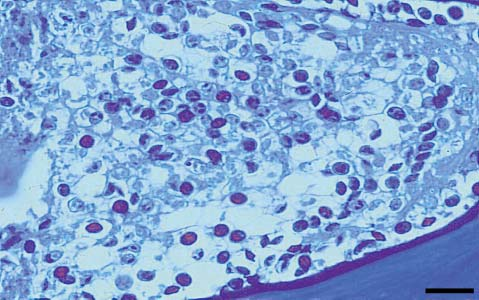

myxosporidi

Myxosporidia-Myxobolidae-Myxobolus-cerebralis-spores-in-the-cartilage-of-rainbow-trout